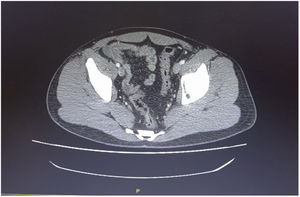

We present herein a case of terminal ileitis related to reactive ileal lymphoid hyperplasia (RILH) that occurred in a patient with underlying COVID-19. A 29-year-old man, a smoker, with an unremarkable past medical history, was admitted to the hospital during Spain’s Omicron coronavirus wave, presenting with acute abdominal pain in the right lower quadrant (RLQ), of 2-day progression, unaccompanied by diarrhea, respiratory symptoms, or fever. He had received an mRNA COVID-19 vaccine 8 months before admission. A nasopharyngeal swab specimen was positive for RT-PCR SARS-CoV-2, with low cycle threshold values. Respiratory auscultation was normal and blood test results showed increased acute phase reactants. No other laboratory test abnormalities were detected. Chest X-ray was normal. Abdominal computed tomography (CT) scan (Fig. 1) revealed marked circumferential bowel wall thickening of the terminal ileum that was suggestive of Crohn’s disease (CD). Because of the suspected diagnosis of CD and/or an associated bacterial co-infection, the patient was empirically started on a broad-spectrum regimen with ceftriaxone, metronidazole, and methylprednisolone at admission, with good clinical outcome. Ileocolonoscopic exploration of 15 cm of the terminal ileum identified slightly edematous and erythematous areas of mucosa, suggestive of indeterminate ileitis. Biopsy taken at the terminal ileum suggested RILH of the lamina propria. No enzyme immunoassays detected other viral or bacterial agents (norovirus, adenovirus, rotavirus, Salmonella spp., Shigella spp., Yersinia enterocolitica, Campylobacter spp. and Clostridioides difficile antibodies) or autoimmune antibodies (antinuclear antibodies [ANA] or antineutrophil cytoplasmic antibodies [ANCA]). IgM serology was negative for SARS-CoV-2 and IgG serology was positive for the virus. Thus, there were no clear clinical (no diarrhea), endoscopic (indeterminate ileitis), or histologic (normal architecture) features that enabled a diagnosis of CD or other conditions, such as infectious ileitis, microscopic enteritis, or autoimmune vasculitis.